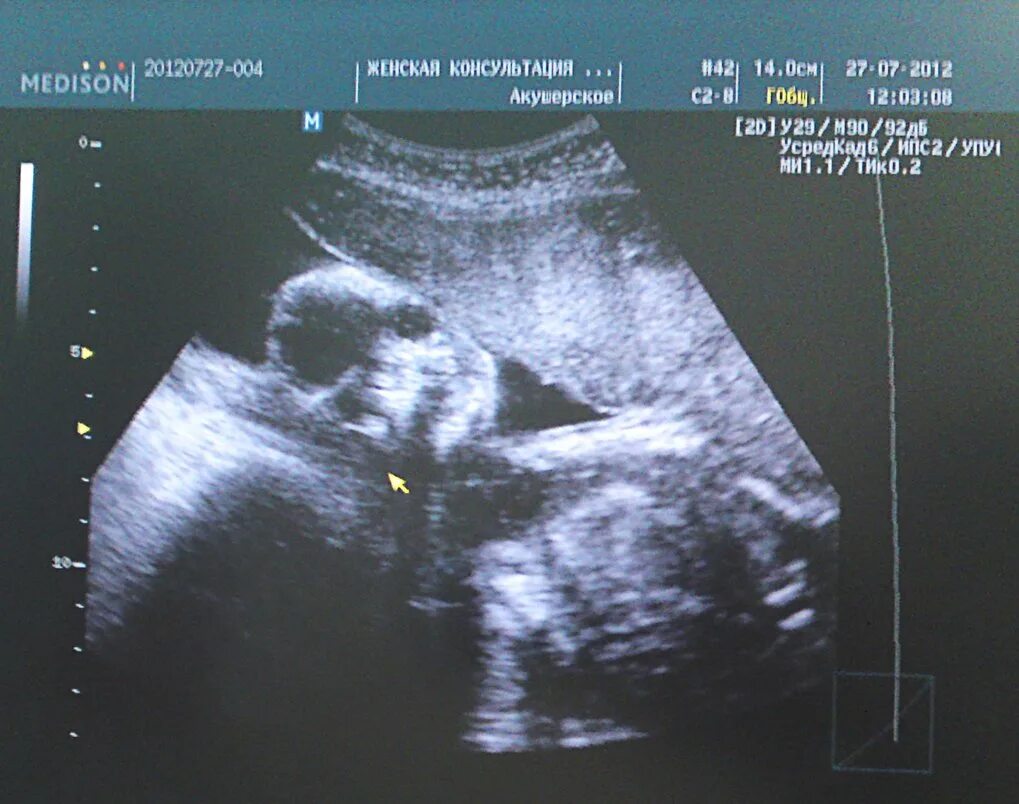

Хороший второй скрининг форум